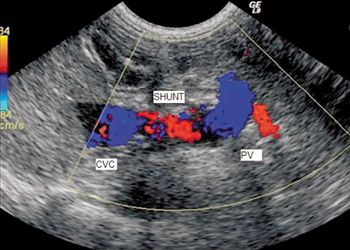

When you have a patient with a hepatic vascular abnormality, how do you confirm it?

Add a little contrast to help you find your diagnosis.

Examine the imaging results to help solve this pug's problem.